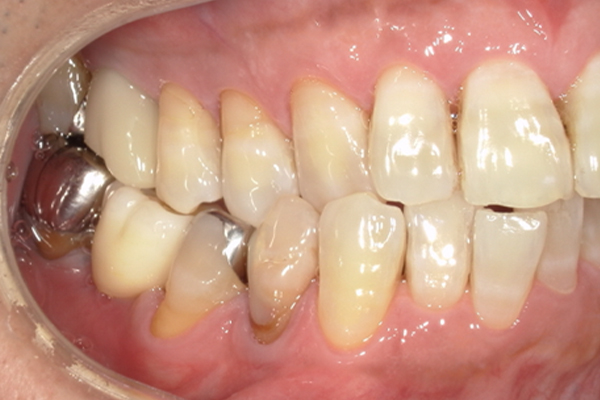

| 主訴 | 奥歯で噛めない、顎が痛い |

|---|---|

| 治療内容 | 奥歯のインプラント治療、前歯・奥歯の被せ物治療 |

| 治療期間 | 6ヶ月 |

| 治療費 | 350万円 |

| 治療リスク | 被せ物をつけた初期の段階で歯がしみることがある(時間とともに改善する) インプラント治療後に3日程度痛みと腫れを伴うことがある |